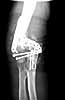

I revised the failed fixation in Nov. 2003. Please see attached file (first revision). The triceps was mangled with its central portion very deficient. I used an olecranon osteotomy.

first revision